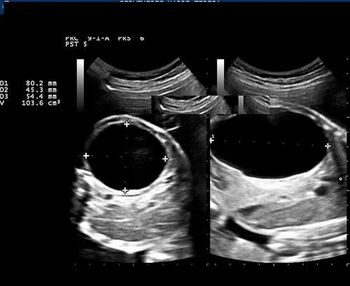

Challenge your diagnostic skills: What's going on with the kidneys in this fetus?